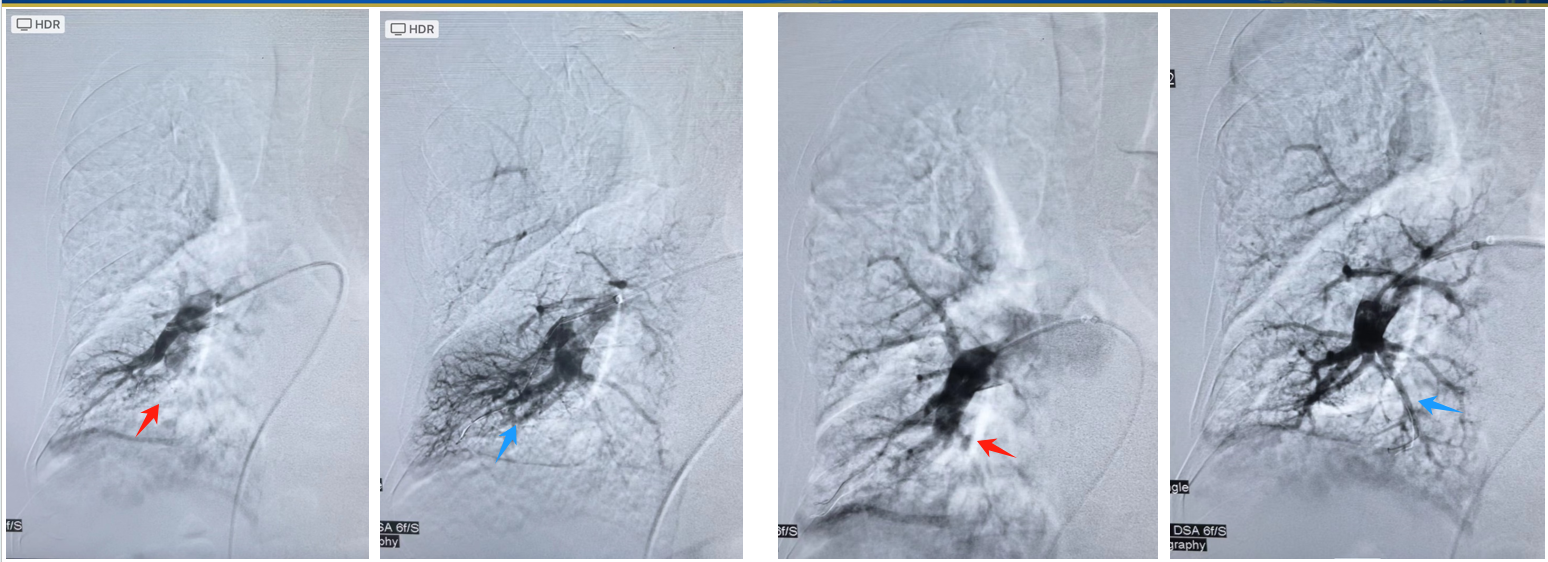

簡單來說,就是肺動脈(連接心臟和肺的血管)里長期有血塊堵住,這些血塊像凍豆腐一樣,導致血管變窄、血流不暢,心臟需要更用力泵血,時間久了心臟負擔加重,可能引發(fā)心衰。為什么會得這個病?主要原因:以前得過肺栓塞(肺部血管被血塊堵住),但血塊沒有完全溶解,慢慢變成“疤痕”一樣的東西,長期堵住血管。其他風險:有反復腿血栓(深靜脈血栓)病史;血液容易凝固(比如某些遺傳病或免疫疾?。?;做過脾臟切除手術(shù)等。有哪些癥狀?早期可能只是“容易累、氣短”,但隨著病情加重,會出現(xiàn):稍微活動就喘不過氣(比如爬樓梯、走路比原來費勁);胸口悶或疼(心臟負擔大);腿腫、肚子脹(因為心臟功能變差,血液回流不暢);突然暈倒(嚴重時心臟供血不足)。??注意:很多患者誤以為是“體質(zhì)變差”或“年紀大了”,耽誤就診!如果曾經(jīng)得過肺栓塞或腿血栓,之后長期氣短,一定要檢查。如何確診?CT肺動脈造影(CTPA):像拍片子一樣,看肺動脈有沒有堵塞。肺灌注掃描(V/Q掃描):非常重要又容易被忽視的檢查,可檢查肺部血流是否正常,尤其是外周小血管的病變。心臟超聲:初步估測心臟壓力和功能,是簡單有效無創(chuàng)的篩選方法。右心導管檢查(確診金標準):醫(yī)生會從脖子或大腿插一根細管到心臟,直接測肺動脈壓力。肺動脈造影:配合右心導管檢查,通過造影圖像,共同明確慢性血栓栓塞性肺動脈高壓診斷。怎么治療?1.手術(shù)——肺動脈內(nèi)膜剝脫術(shù)(PEA)適合誰?血栓主要在大的肺動脈,且身體能承受手術(shù),因該手術(shù)需要在亞低溫心臟停跳情況下完成,手術(shù)難度大。效果:多數(shù)人術(shù)后癥狀明顯改善,甚至可能治愈。風險:手術(shù)較大,需要在有經(jīng)驗的醫(yī)院做。2.微創(chuàng)治療——肺動脈球囊成形術(shù)(BPA)用小球囊撐開狹窄的肺動脈,適合遠端小血管堵塞或不能手術(shù)及不愿行PEA手術(shù)的患者。部分患者經(jīng)過多次肺動脈球囊成形術(shù)治療后,其肺動脈高壓甚至可以回落至正常范圍,達到類似PEA手術(shù)的效果。3.藥物抗凝藥:如華法林、利伐沙班,防止新血栓形成(需長期甚至終身服用)。降肺動脈壓藥:如利奧西呱,幫助擴張血管、減輕心臟負擔(適合不能手術(shù)或術(shù)后仍有高壓的患者)。

肺動脈高壓(pulmonaryhypertension,PH)是常見的肺血管疾病,是一種嚴重危害人類健康的疾病。一、定義與臨床分類肺動脈高壓(PH)是指各種原因?qū)е碌姆蝿用}壓力異常增高的疾病或病理生理綜合征,存在肺循環(huán)障礙和右心高負荷,最終可導致右心衰竭甚至死亡。肺動脈高壓既可來源于肺血管自身的病變,也可繼發(fā)于其他心、肺或系統(tǒng)性疾病等。肺動脈高壓的血流動力學標準為:海平面、靜息時、右心導管測量平均肺動脈壓(mPAP)≥25mmHg(1mmHg=0.133kPa)。肺動脈高壓臨床分類仍舊延續(xù)既往五大類分類原則,包括1.動脈性肺動脈高壓(PAH);2.左心疾病所致肺動脈高壓;3.肺部疾病和(或)缺氧所致肺動脈高壓;4.肺動脈阻塞性疾病所致肺動脈高壓;5.未知因素所致肺動脈高壓;二、肺動脈高壓的分級(一)根據(jù)超聲心動圖所估測的肺動脈收縮壓(PASP),根據(jù)其嚴重程度將其分為三個等級:輕度肺動脈高壓:35≤PASP≤49mmHg中度肺動脈高壓:50≤PASP≤69mmHg重度肺動脈高壓:PASP≥70mmHg(二)根據(jù)超聲心動圖所估測的平均動脈壓(mPAP),根據(jù)其嚴重程度將其分為四個等級:一級(輕度):mPAP在26-35mmHg之間,此時患者可能癥狀較輕,甚至無明顯自覺癥狀。日?;顒踊静皇芟?,但在進行較為劇烈的體力活動時,可能會出現(xiàn)輕微的呼吸困難、乏力等表現(xiàn)。例如,爬樓梯時可能會比以往稍感氣喘,但稍作休息即可緩解。二級(中度):mPAP為36-45mmHg?;颊咴谌粘;顒又袝幸欢ǔ潭鹊氖芟蓿绮叫幸欢尉嚯x后就會感到氣短,需要停下來休息??赡苓€會伴有心悸、胸痛等癥狀,尤其是在勞累后癥狀會更加明顯。三級(重度):mPAP達到46-55mmHg。患者的體力活動明顯受限,即使是輕微的活動,如穿衣、洗漱等,也可能引發(fā)嚴重的呼吸困難、頭暈、昏厥等癥狀。心臟功能已經(jīng)受到較大影響,右心衰竭的風險顯著增加。四級(極重度):mPAP超過55mmHg。這是最嚴重的階段,患者常常處于靜息狀態(tài)下也會有呼吸困難、胸痛、水腫等癥狀,生活難以自理,生命安全受到嚴重威脅,隨時可能發(fā)生心源性猝死等危及生命的情況。三、臨床表現(xiàn)肺動脈高壓(pulmonaryhypertension,PH)患者臨床癥狀無特異性,可出現(xiàn)呼吸困難、干咳、暈厥、胸悶、胸痛和疲勞,多于活動后明顯,重癥患者臨床體征多為右心功能不全的表現(xiàn),可有頸靜脈充盈、肝淤血、下肢、腹部甚至全身水腫。一部分臨床表現(xiàn)與PH的肺血流的異常分布和并發(fā)癥相關(guān),包括咯血、喘息、聲音嘶啞、胸痛等。咯血是由于血管重構(gòu)、低氧性血管收縮和微血栓形成,肺循環(huán)血量減少,支氣管動脈側(cè)支血管生成,并逐漸擴張,因局部血壓增高而破裂,并滲漏到氣管支氣管樹中,導致咯血。大氣道受壓引起喘息,肺動脈擴張后左喉返神經(jīng)受壓引起聲音嘶啞,左冠狀動脈主干受壓引起的心肌缺血所致心絞痛樣胸痛。嚴重肺動脈擴張可引起肺動脈破裂或夾層,導致心臟填塞的體征和癥狀。PH的心臟體征包括第二心音亢進及固定分裂、奔馬律、部分患者出現(xiàn)胸骨左緣三尖瓣關(guān)閉不全的收縮期反流性雜音,肺動脈瓣相對狹窄的收縮期雜音及舒張期Gram-stell雜音。某些體征可能提示PH的潛在原因。硬皮病中可見毛細血管擴張、肢端潰瘍和硬化,吸氣相爆裂音(Velcro啰音)可能提示間質(zhì)性肺疾病,蜘蛛痣、睪丸萎縮和肝掌提示肝病。遺傳性出血性毛細血管擴張癥可見四肢末端出現(xiàn)毛細血管擴張。當遇到杵狀指時,應考慮肺靜脈閉塞病/肺毛細血管瘤病、紫紺型先天性心臟病或間質(zhì)性肺疾病可能。四、診斷性檢查(一)心電圖心電圖可能提供PH的支持性證據(jù),但心電圖正常不能排除該診斷。心電圖異常見于嚴重PH,PH心電圖異常可表現(xiàn)為QRS電軸右偏、QTc間期延長、肺性P波、右束支傳導阻滯、右心室肥厚等。QRS波群和QTc間期延長提示病情嚴重。(二)胸部X線PH患者胸部X線表現(xiàn)如下:右下肺動脈擴張,肺動脈段凸出,中心肺動脈擴張和外周分支纖細,形成"殘根"征,還可見右心房和右心室擴大。胸部X線還可用于發(fā)現(xiàn)心肺疾病的一些影像學改變,有助于病因篩查。正常的X線胸片亦不能排除PH,其嚴重程度與胸片異常程度并無相關(guān)性。(三)動脈血氣分析和肺功能動脈血氣分析在氣道阻塞性疾病及神經(jīng)肌肉疾病中表現(xiàn)為低氧血癥及高碳酸血癥。輕癥動脈性肺動脈高壓(pulmonaryartialhypertension,PAH)的動脈血氣分析可完全正常,重癥患者可出現(xiàn)低氧后代償性過度通氣,過度通氣的程度反映了供氧障礙、肺血管疾病、心功能障礙的程度,具體表現(xiàn)為PaO2和PaCO2下降。特發(fā)性肺動脈高壓(idiopathicpulmonaryarteryhypertension,IPAH)患者PaO2和預后無明確相關(guān)性,而PaCO2越低,表明過度通氣越嚴重,預后將越差。當出現(xiàn)與疾病嚴重程度不相符的低氧血癥時,需考慮動靜脈分流的情況。肺功能檢查在第三大類PH的病因診斷中具有較高價值,對于呼吸系統(tǒng)疾病所致的PH,根據(jù)FVC、第1秒用力呼氣肺容積(forcedexpiratoryvolumeinthefirstsecond,F(xiàn)EV1)、DLCO、肺總量(totallungcapacity,TLC)可以鑒別阻塞性、限制性以及混合性通氣功能障礙的肺部疾病。間質(zhì)性肺疾病相關(guān)PH與胸膜增厚、胸廓畸形等在肺功能的表現(xiàn)上相似,均表現(xiàn)為肺容積的減少,部分原因為右心室的擴張和肥厚。PAH患者可出現(xiàn)輕度限制性通氣功能障礙,彌散功能可表現(xiàn)為輕或中度下降,也可引起輕度氣道阻塞。(四)超聲心動圖超聲心動圖不僅可用于疑診PH的篩查,而且對于病因鑒別及心功能評價亦有很大幫助。超聲心動圖可以測量靜息狀態(tài)下的三尖瓣反流峰值流速和其他指標用以評估PH的可能性。對于疑診PH的患者,可根據(jù)超聲心動圖評估的可能性作進一步檢查。超聲心動圖有助于鑒別PH的病因,如左心疾病、先天性心臟病等。超聲心動圖還可根據(jù)三尖瓣環(huán)收縮期位移(tricuspidannularplanesystolicexcusion,TAPSE)、右心室面積變化分數(shù)、右心室心肌做功指數(shù)、左心室偏心指數(shù)等評估患者的右心功能,并可預測預后。TAPSE可評價右心室心肌縱向收縮功能,TAPSE<18mm提示右心室心肌縱向收縮功能異常改變,是PH患者死亡的獨立危險因素。右心室面積變化分數(shù)反映了右心室縱向以及橫向的收縮功能,正常人右心室面積變化分數(shù)>35%,如果右心室面積變化分數(shù)<35%提示PH患者RVEF減低,右心室面積變化分數(shù)可以預測PH患者的預后。右心室心肌做功指數(shù)是反映右心室整體舒張功能與收縮功能的指標,升高提示右心室功能減退。經(jīng)食道超聲和右心聲學造影對于第一大類PH中先天性心臟病的診斷更為精確。經(jīng)食道超聲心動圖是經(jīng)胸超聲心動圖的重要補充,當某些原因引起的經(jīng)胸超聲心動圖無法明確診斷時(如肺氣腫、重度肥胖或要觀察心臟深部的結(jié)構(gòu),如左心耳、降主動脈),經(jīng)食道超聲心動圖更有其優(yōu)越性。對于房間隔缺損,經(jīng)食道超聲心動圖檢查更能精確地觀察缺損殘端的硬度、測量缺損的大小、測量缺損距上、下腔靜脈、房室瓣、肺靜脈的距離從而選擇適宜的手術(shù)方案。右心聲學造影適應癥包括:(1)診斷某些先天性心血管畸形;(2)疑有心腔內(nèi)分流的疾病,可明確有無左向右或右向左分流,并可估計分流量大小;(3)需了解瓣膜反流、心內(nèi)膜邊緣、室壁厚度、右心腔大小、有無占位等;(4)可改善三尖瓣和肺動脈血流頻譜多普勒信號;(5)查找低氧血癥的病因。相對禁忌癥主要包括:(1)重度PH者;(2)呼吸功能不全、嚴重肺氣腫、重癥貧血患者;(3)重癥紫紺患者伴心內(nèi)大量分流者;(4)嚴重心、腎功能不全、酸中毒患者;(5)有栓塞病史者;(6)急性冠狀動脈綜合征患者。(五)核素肺通氣/灌注(ventilation/perfusion,V/Q)顯像核素肺V/Q顯像可用于第四大類PH中肺動脈狹窄或閉塞性病變的篩查,尤其是存在通氣與灌注不匹配,且為肺段分布的灌注缺損時則可能性大。PAH的V/Q顯像可能存在非肺段性灌注缺損,也可能正常。篩查慢性血栓栓塞性肺動脈高壓(chronicthromboembolicpulmonaryhypertension,CTEPH)首選V/Q顯像,其比CT肺動脈造影(computertomographypulmonaryangiography,CTPA)敏感度高,當V/Q顯像正?;虻投瓤赡芸苫九懦鼵TEPH。但需注意,當存在嚴重心肺部疾病時,V/Q顯像易出現(xiàn)假陽性,需結(jié)合其他檢查進行鑒別。(六)胸部CT胸部CT可顯示關(guān)于實質(zhì)、縱隔、心臟、血管異常的信息,若出現(xiàn)主肺動脈擴張、右心房和右心室擴大,主肺動脈直徑大于等于升主動脈直徑時要考慮PH。高分辨CT有助于第三大類PH病因篩查,例如間質(zhì)性肺疾病、肺氣腫、肺大皰、支氣管擴張、淋巴結(jié)異常、胸腔積液等肺部病變,若發(fā)現(xiàn)縱隔淋巴結(jié)腫大、彌漫性小葉中心性磨玻璃結(jié)節(jié)、小葉間隔增厚等征象則需考慮肺靜脈閉塞病/肺毛細血管瘤可能;若發(fā)現(xiàn)肺動脈擴張、中葉肺不張和對應側(cè)胸腔積液需考慮纖維性縱隔炎(fibrinousmediastinum,F(xiàn)M)。CTPA對診斷肺血管病有重要價值,CTEPH患者行CTPA可見肺動脈內(nèi)網(wǎng)狀充盈缺損、肺動脈管壁不規(guī)則的增厚、部分可見條帶影、甚至肺動脈完全阻塞等。CTPA還可作為CTEPH患者制定治療方案時的重要參考,為肺動脈血栓內(nèi)膜剝脫術(shù)(pulmonarythromboendarterectomy,PEA)、球囊肺動脈成形術(shù)(balloonpulmonaryangioplasty,BPA)提供影像學依據(jù)。(七)肺動脈造影肺動脈造影術(shù)是診斷肺栓塞的"金標準",其可顯示血管狹窄、充盈缺損及血管截斷等表現(xiàn),但因其為有創(chuàng)操作,目前已被CTPA所取代。右心導管檢查(rightheartcatheterization,RHC)及肺動脈造影用于CTEPH患者,不僅可顯示其栓塞位置、范圍、大小及嚴重程度,評估病變類型,還可為該類患者選擇合適的治療手段提供依據(jù)。對于一些重癥患者無法行PEA,或者病變遠端,PEA無法企及的部位,或者合并其他并發(fā)癥的患者,可考慮行BPA。肺動脈造影還可行肺動脈內(nèi)膜活檢術(shù)以及先天性心血管疾病的診斷等。(八)心血管磁共振心血管磁共振(cardiacmagneticresonance,CMR)成像可評價右心室形態(tài)、大小和功能及血流量,包括心輸出量和右心室質(zhì)量。當出現(xiàn)肺動脈擴張減少、逆行血流和晚期釓增強時,需要疑診PH,但單一CMR測量均不能排除PH。MR血管造影可鑒別導致肺血管堵塞的病因,尤其適用于孕婦或?qū)Φ庠煊皠┻^敏者。CMR對右心功能的評估與RHC相比具有較高的一致性,可測量右心室功能和容積、左心室功能等,可預測生存率,還可用于評估PH靶向藥物治療效果,因而可作為PAH患者基線和隨訪時對病情嚴重性判斷的手段。因為CMR具有無創(chuàng)、可重復的特點,CMR測量右心房容積可預測PH患者的臨床結(jié)局,當出現(xiàn)雙心室應變明顯受損,可早期發(fā)現(xiàn)右心和左心功能障礙。(九)血液學檢查血液學檢查主要用于篩查PH的病因和評價器官損害情況。血細胞分析異常要警惕血液系統(tǒng)疾病、慢性缺氧性疾病以及結(jié)締組織疾病等。肝功能異常需考慮藥物損傷、門靜脈高壓、心力衰竭及血液系統(tǒng)疾病等原因。當風濕免疫病相關(guān)自身抗體、人類免疫缺陷型病毒(humanimmunodeficiencyvirus,HIV)抗體、肝炎標志物等異常時,需考慮風濕疾病相關(guān)、HIV相關(guān)等特殊PH。CTEPH患者需行易栓癥篩查(包括遺傳性和獲得性),尤其需排除抗磷脂抗體綜合征。對于原因不明的兒童PH患者,需明確是否存在代謝性疾病(如甲基丙二酸尿癥等)。所有PH患者均需測定血液腦鈉肽(brainnatriureticpeptide,BNP)或N末端腦鈉肽前體(N-terminalpro-brainnatriureticpeptide,NT-proBNP),在初診及隨訪過程中用于評估病情及指導治療。高尿酸可提示IPAH患者預后不良。肌鈣蛋白T和肌鈣蛋白I是急性冠狀動脈綜合征和急性肺栓塞的預后指標,肌鈣蛋白T升高是患者死亡的獨立預測因子,部分患者治療后肌鈣蛋白T暫時或永久消失。心房利鈉肽和BNP有相似的生理功能,是心臟壁受壓時由心肌釋放,均能導致血管擴張和尿鈉增多。BNP/NT-proBNP水平升高,提示右心衰竭,是PAH患者最主要的死亡原因。(十)腹部超聲腹部超聲可以確診但不能完全排除門靜脈高壓,可以了解腹部臟器的結(jié)構(gòu)和功能,為第一大類中門脈高壓性PH的病因篩查提供依據(jù)。(十一)RHC和急性血管反應試驗RHC是診斷和評價PH的金標準,可獲得腔靜脈壓、右心房壓、右心室壓、肺動脈壓、肺動脈楔壓、混合靜脈血氧飽和度(mixedvenousoxygensaturation,SvO2)、心輸出量和肺血管阻力等血流動力學數(shù)據(jù)。根據(jù)指南推薦,成人PAH患者的危險分層包括RHC測量的右心房壓和SvO2,建議在專業(yè)的PH中心行RHC,RHC用途廣泛,可用于器官移植前(對因左心疾病或肺部疾病引起的PH)的評估、判斷有無心內(nèi)左向右分流、可確診CTEPH、用于PAH的診斷及病因篩查、可輔助鑒別診斷、評價對肺血管擴張劑的反應性。RHC絕對禁忌癥為導管進入路徑部位有感染。相對禁忌證包括:(1)嚴重心律失常,尤其是室性心律失常;(2)嚴重的心力衰竭或嚴重的PAH未改善者;(3)急性感染性疾??;(4)嚴重凝血機制障礙;(5)電解質(zhì)紊亂;(6)不能配合進行RHC。對于PAH患者,可行急性血管反應試驗(先天性心臟病伴有肺內(nèi)嚴重分流肺疾病的患者除外),若為陽性則口服鈣通道阻滯劑有效,可以延長生存期,建議長期口服,定期隨訪,陽性患者預后較好。急性血管反應試驗陽性率為10%。有文獻報道使用肺血管擴張藥物的PH患者如果出現(xiàn)肺水腫時,需要考慮肺靜脈閉塞病的可能。(十二)基因檢測基因檢測對PAH患者具有重要意義。可以找到患者病因,預測疾病的發(fā)生、發(fā)展,為疾病的診斷、治療提供理論依據(jù);建議對遺傳性PAH患者及親屬、IPAH患者、遺傳性出血性毛細血管擴張癥患者及其親屬、疑診肺靜脈閉塞病/肺毛細血管瘤病的患者、肺靜脈閉塞病/肺毛細血管瘤病患者父母及子女進行相關(guān)基因的篩查。五、治療不同類型的PH治療措施不同,如果是疾病相關(guān)的肺動脈高壓,以治療原發(fā)病為主。對于CTEPH,肺動脈血栓內(nèi)膜剝脫術(shù)(PEA)為首選治療。對于PAH,近些年治療藥物不斷增加,治療方案也在不斷變化。PAH的治療可分為三個主要步驟:一是起始治療,包括避孕、康復及運動訓練、擇期手術(shù)、預防感染、心理支持、避免出行高海拔或低氧地區(qū)的一般性措施和口服抗凝藥、利尿劑、吸氧、地高辛、補充鐵劑等支持性治療;二是個體化的藥物治療,對于急性肺血管反應試驗陽性的IPAH、遺傳性PAH及藥物相關(guān)PAH患者應給予大劑量鈣離子拮抗劑(CCB)治療,包括硝苯地平、地爾硫卓、氨氯地平,CCB的選擇需要根據(jù)基礎心率情況決定,CCB應從低劑量用起,逐漸增加至可耐受的最大劑量。對急性肺血管反應試驗陰性的患者可使用靶向藥物單藥或聯(lián)合治療,根據(jù)危險分層制定治療和隨訪策略,中、高?;颊咄扑]初始和(或)序貫聯(lián)合治療;三是右心功能維護及終末期治療:對于出現(xiàn)右心衰竭的患者,指南推薦包括治療誘發(fā)因素、優(yōu)化容量管理、降低右心室后負荷、應用正性肌力藥等治療原則。經(jīng)充分的內(nèi)科藥物治療仍合并嚴重血流動力學受損、運動耐量顯著降低和明顯右心衰竭征象的肺高血壓患者可考慮行肺移植或心肺聯(lián)合移植。六、我國常見肺動脈高壓亞類(一)動脈性肺動脈高壓(PAH)為第一類肺動脈高壓,其中先天性心臟相關(guān)的肺動脈高壓(CHD-PAH)和結(jié)締組織疾病相關(guān)的肺動脈高壓(CTD-PAH)常見。CHD-PAH是指體-肺分流型先天性心臟病所引起的肺動脈壓力升高,是毛細血管前型肺動脈高壓的一種。臨床分為艾森曼格綜合征、體肺分流性先天性心臟病、肺動脈高壓并發(fā)先天性心臟病、先天性心臟病術(shù)后肺動脈高壓.。根據(jù)體-肺分流程度分為動力型和阻力型。治療方案應該根據(jù)PAH程度決定,對于動力型患者,手術(shù)是根本的方法;對于阻力型患者,可以采用靶向藥物治療和心肺聯(lián)合移植或肺移植聯(lián)合心臟缺損修補術(shù)。肺動脈高壓是導致結(jié)締組織疾病死亡的重要原因,因此早期篩查、早期診斷和早期治療意義重大。早期篩查包括一方面CTD患者一旦出現(xiàn)氣短、胸痛、咯血等PAH相關(guān)癥狀,應盡快進行PAH篩查,另一方面對確診PAH的患者也要盡早進行PAH篩查。治療方案根據(jù)CTD病情是否活動及PAH是否達標來決定?;ACTD治療如糖皮質(zhì)激素聯(lián)合免疫抑制劑等對改善和穩(wěn)定病情至關(guān)重要,方案亦需要個體化。PAH治療分為一般治療和肺血管擴張治療。波生坦、馬昔騰坦、司來帕格均可以降低患者臨床惡化或死亡風險。(二)左心疾病相關(guān)性肺動脈高壓(LHD-PH)為第二類肺動脈高壓,患病率約占肺動脈高壓的1/3,是由左心收縮、舒張功能障礙和或左心瓣膜疾病引起的肺動脈壓力異常增高。通常經(jīng)過仔細詢問病史、查體、心電圖、超聲心動圖及其它影像學檢查比較容易在左心疾病特別是在左心衰竭患者中發(fā)現(xiàn)肺動脈高壓。對于LHD-PH,首先應針對左心基礎疾病的有效治療,包括使用利尿劑、硝酸酯類藥物、ACE、β受體阻滯劑和正性肌力藥物,或進行左心室輔助裝置、瓣膜手術(shù)、再同步化治療或心臟移植的介入或手術(shù)治療。目前對此類患者不推薦靶向藥物治療。(三)呼吸系統(tǒng)疾病和(或)缺氧所致肺動脈高壓為第三類肺動脈高壓,是非常常見的一類肺動脈高壓。病因包括慢性阻塞性肺疾病(COPD)、間質(zhì)性肺疾病(IID)、睡眠呼吸暫停綜合癥(OSAHS)、結(jié)節(jié)病等,其中COPD是最常見的病因。呼吸系統(tǒng)疾病相關(guān)肺動脈高壓(PD-PH)患者臨床表現(xiàn)包括兩部分,即基礎疾病的相關(guān)表現(xiàn)和肺動脈高壓引起的癥狀體征。輔助檢查中,超聲心動圖作為估測肺動脈壓力的無創(chuàng)檢查方法有重要價值,但由于檢查結(jié)果會受到肺氣腫的影響以及檢查醫(yī)生個人技術(shù)的限制,所以準確性會降低,金標準仍然是右心導管檢查。治療上針對肺部原發(fā)疾病、低氧患者進行氧療是關(guān)鍵,不推薦使用PAH靶向藥物治療。對于合并嚴重肺動脈高壓病人,建議到肺動脈高壓中心評估。(四)慢性血栓栓塞性肺動脈高壓(CTEPH)屬于第四類肺動脈高壓,也是可能治愈的肺動脈高壓。CTEPH是由于肺血栓機化、肺血管重構(gòu)致肺動脈壓力進行性升高,最終導致右心功能衰竭的一種疾病。CTEPH的診斷標準為經(jīng)過3個月以上的規(guī)范抗凝治療后,影像學證實存在慢性血栓,右心導管檢查mPAP≥25mmHg,且除外其他病變,如血管炎、肺動脈肉瘤、纖維素性縱隔炎等。目前,肺通氣灌注掃描被公認為CTEPH的首選篩查方法,肺動脈造影和右心導管檢查是CTEPH影像學診斷和手術(shù)評估的金標準。CTEPH治療包括長期抗凝治療、家庭氧療、利尿劑和康復治療等基礎治療,以及藥物治療、介入治療和手術(shù)治療。其中肺動脈血栓內(nèi)膜剝脫術(shù)(PEA)是最有效的治療方法,部分患者可通過手術(shù)治愈,但需要在有經(jīng)驗的中心進行評估。部分無法進行PEA的患者可以進行球囊肺動脈成形術(shù)(BPA)治療。靶向藥物可以用于無法進行PEA手術(shù)或術(shù)后殘余肺動脈高壓患者,目前研究比較充分的藥物是可溶性鳥苷酸環(huán)化酶(sGC)激活劑,如利奧西胍等。